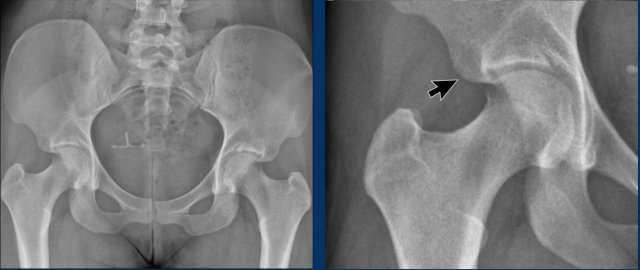

This is a more subtle case of Cam morphology in a young male.

Notice that the epiphyseal plates have not yet closed (arrow).

Images

Two examples of Cam morphology.